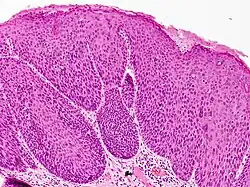

Bowenoid papulosis